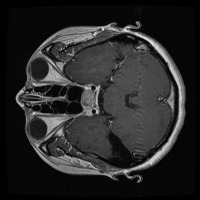

Early Detection of Brain Tumors: Use the "tesis" model to analyze MRI scans of patients proactively during routine check-ups, helping in the early identification of the presence of lesion selar or tumor hipofisario, leading to timely and potentially life-saving interventions.

Assisting in Treatment Planning: Oncologists and neurosurgeons can use the "tesis" model to study the location, size, and class of a patient's tumor. This helps in determining the best treatment options and surgical approaches, ultimately improving patient outcomes.

Medical Education and Training: Incorporate the "tesis" model in medical school curricula and professional trainings aimed at educating future doctors and radiologists about the identification and treatment of lesion selar and tumor hipofisario.

Research Tool for Cancer Studies: The "tesis" model can serve as a tool for researchers working on experimental treatments or clinical trials focused on lesion selar and tumor hipofisario. By identifying tumor classes efficiently and consistently, the model can help researchers compare treatment efficacy and study tumor progression over time.

Second Opinion Provider: Medical professionals can use the "tesis" model to double-check their own findings when analyzing brain MRI scans. This can reduce the likelihood of diagnostic errors and help confirm the presence of lesion selar or tumor hipofisario, resulting in more accurate decision-making.